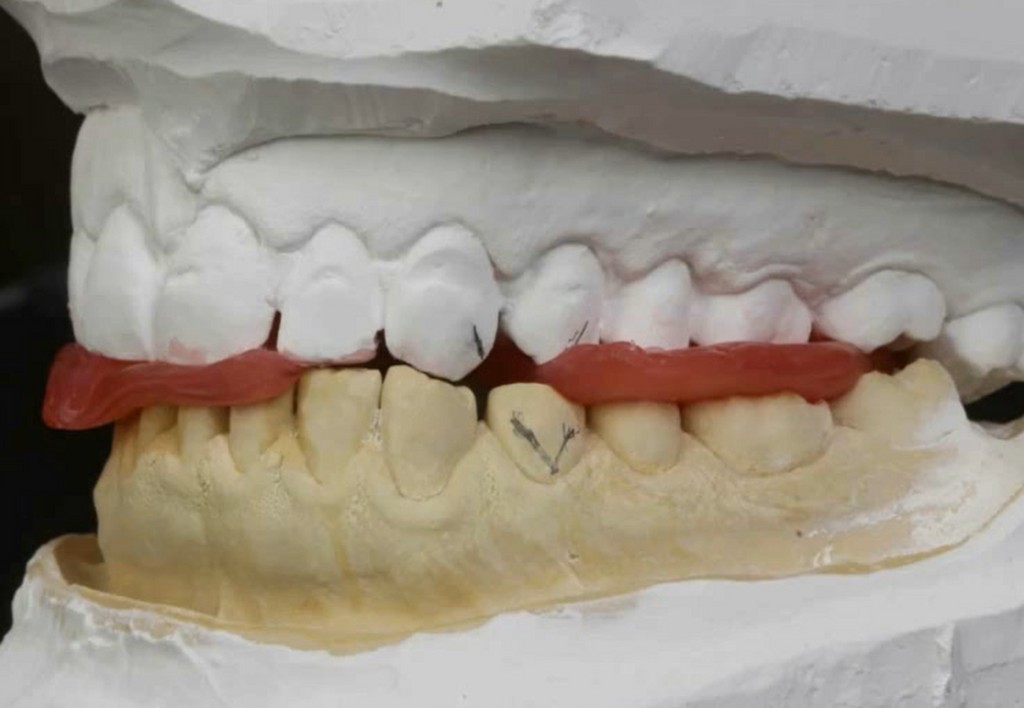

► Mock-up e pre-visualizzazione

► Creazione di un indice in silicone trasparente

Galleria fotografica